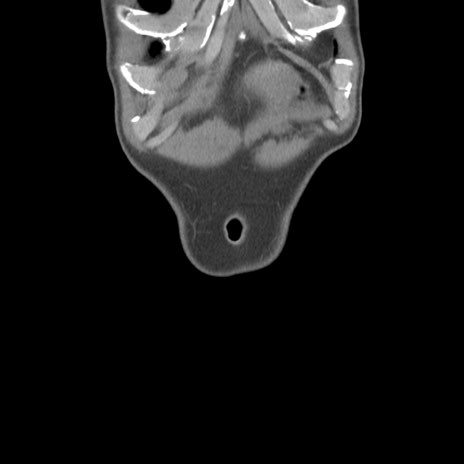

症例56 CT(冠状断像)

脂肪ウインドウ

横断像